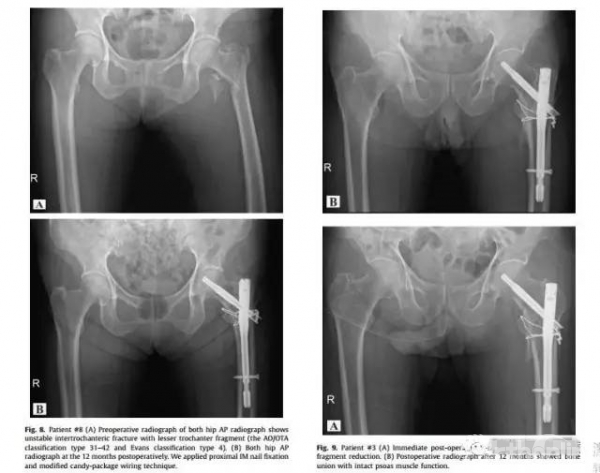

作者采用回顾性研究方法,选取所在机构自2014年1月至2015年6月之间接受股骨近端髓内钉及微创“糖果包裹”钢丝捆扎技术的不稳定转子间骨折患者,共纳入符合标准的22名患者,该组患者平均年龄为75.8岁(范围53-88岁),平均随访期为15.1个月(范围12-24月)。每位患者随访至少12个月,并对其临床和放射结果进行分析。

结果:骨折愈合所需的平均时间为16.6周(范围:8-25周),经随访,该组病例骨折均达骨折愈合标准。WOMAC评分在最后一次随访中平均为45.4(范围:21-75),与伤前的状态(平均36.5,范围:19-59)没有显著差异(p=0.087)。与创伤前的行走能力相比,有4例病例中(18.2%)疗效差,有18例(81.8%)得到恢复。2例病人出现术后钢丝断裂,1例病人出现髋关节异位骨化,术后影像学资料显示复位良好,没有螺钉切割、断裂及螺钉的松动退出并发症发生。

结论:采用股骨近端髓内钉及改良“糖果包裹”钢丝捆扎技术治疗不稳定转子间骨折合并小转子骨折,经过改进后的“糖果包裹”钢丝布线技术,提高了骨折部位的固定力量,通过这一技术,不但完美复位了小转子骨折的移位,也提高了该部位骨折的愈合率。